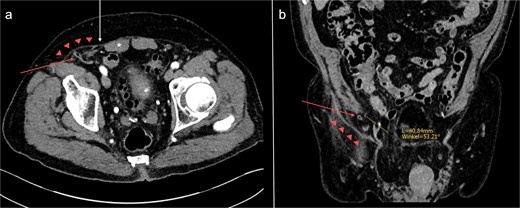

An 87-year-old male on oral anticoagulant therapy was admitted to the emergency department with abdominal pain for 1 week. On physical examination, a painful mass could be palpated in the right lower quadrant of the abdomen, accompanied by local signs of inflammation. Blood tests revealed elevated levels of C-reactive protein (CRP) and white blood cells (WBC). The patient had no history of previous surgery in the lower abdomen. A computed tomography (CT) scan showed a large fluid collection in the abdominal wall, primarily interpreted as a superinfected hematoma (Fig. 1). Incision and drainage of the collection was performed, which released large quantities of pus. Consequently, the patient was put on broad-spectrum antibiotics.

Abdominal CT-scans on initial presentation (a) and day 5 (b). A large fluid collection (*) can be seen in the right lower abdominal wall. After drainage, the appendix (white arrow) could be identified inside the abscess cavity, indicating the existence of a PVH.

During the following days, purulent discharge from the wound continued and the patient developed signs of sepsis. Abdominal CT was repeated, which now revealed acute appendicitis inside an atypical PVH in the right peri-inguinal region (Fig. 1). Thus, the patient was taken back to the operating room for laparoscopy and abdominal wall exploration. Intraoperatively, a segment of terminal ileum and the appendix were found trapped inside the hernia orifice (Fig. 2). After reduction of the herniated contents, laparoscopic appendectomy was performed uneventfully. The remaining abscess cavity was generously incised, debrided and left open to facilitate secondary wound closure (Fig. 3). This was eventually achieved using a vacuum-assisted closure (VAC) device and secondary suture. After management of concomitant medical conditions, the patient was discharged from the hospital on the 11th postoperative day. No physical follow-up was conducted as the patient declined further surgery for hernia repair due to poor general condition.